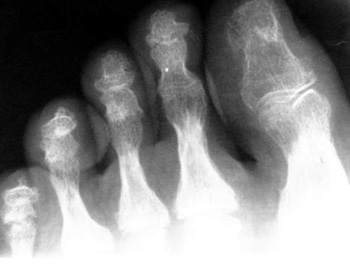

Ревматические процессы в околосуставных тканях относятся к внесуставным заболеваниям мягких тканей опорнодвигательного аппарата, часто объединяемым под общим названием "внесуставный ревматизм". В эту большую группу различных по своему происхождению и клинике патологических процессов входят заболевания как тканей, расположенных в непосредственной близости к суставам, т. е. околосуставных тканей (сухожилия мышц, их влагалища, слизистые сумки, связки, фасции и апоневрозы), так и тканей, находящихся на некотором отдалении от суставов (мышцы, нервнососудистые образования, подкожная жировая клетчатка).

К этим процессам в первую очередь относятся тендиниты, тендовагиниты, бурситы, тендобурситы, лигаментиты, а также фиброзиты.